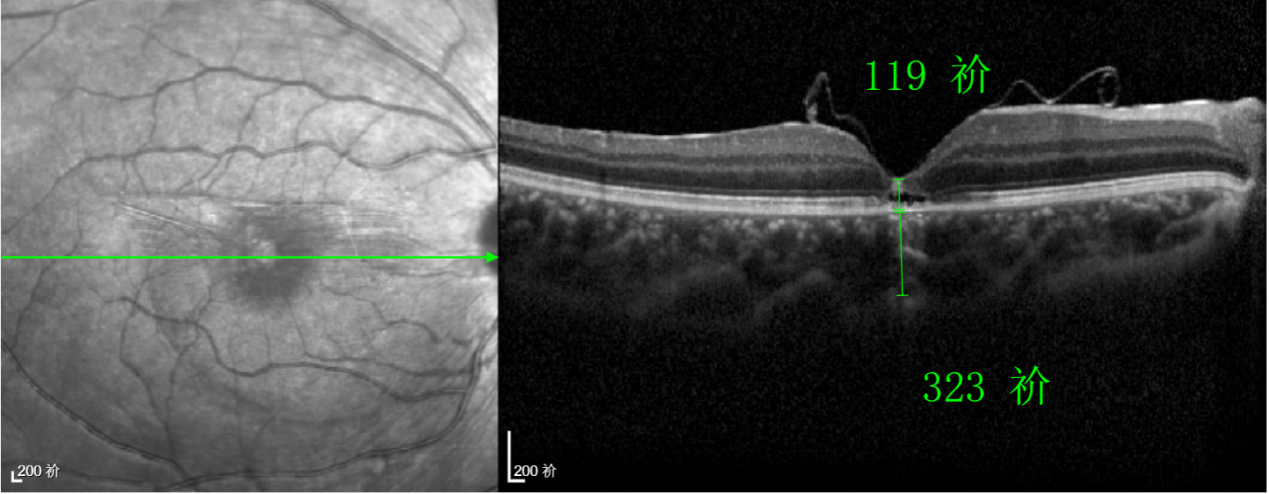

除此之外,利用自體組織覆蓋為黃斑裂孔提供了理想的愈合環(huán)境,裂孔閉合速度顯著快于傳統(tǒng)方法。誠(chéng)誠(chéng)接受手術(shù)24小時(shí)后,檢查可見(jiàn)內(nèi)界膜瓣位置良好;術(shù)后1個(gè)月,黃斑裂孔已經(jīng)閉合,視力恢復(fù)到0.5;術(shù)后兩個(gè)月,視力進(jìn)一步提升到0.7。

“書(shū)本的文字都變直了,黑板上的字也更清晰了!”

術(shù)后3個(gè)月復(fù)查時(shí),小男孩的眼睛閃耀著自信的光芒。